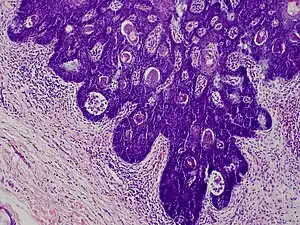

Folliculosebaceous cystic hamartoma abbreviated as (FSCH) is a rare cutaneous hamartoma consisting of dilated folliculosebaceous units invested in mesenchymal elements.[1]: 676 it typically affects adults, have a predilection for the central face or scalp, with less than 1.5 cm dimension.[2] Clinically, the lesions are asymptomatic, rubbery to firm in consistency, and usually occur on or above the neck in (> 90%) of cases, Histopathologically, FSCH shares several similar features to sebaceous trichofolliculoma, but it is usually possible to differentiate these two tumors.[3]